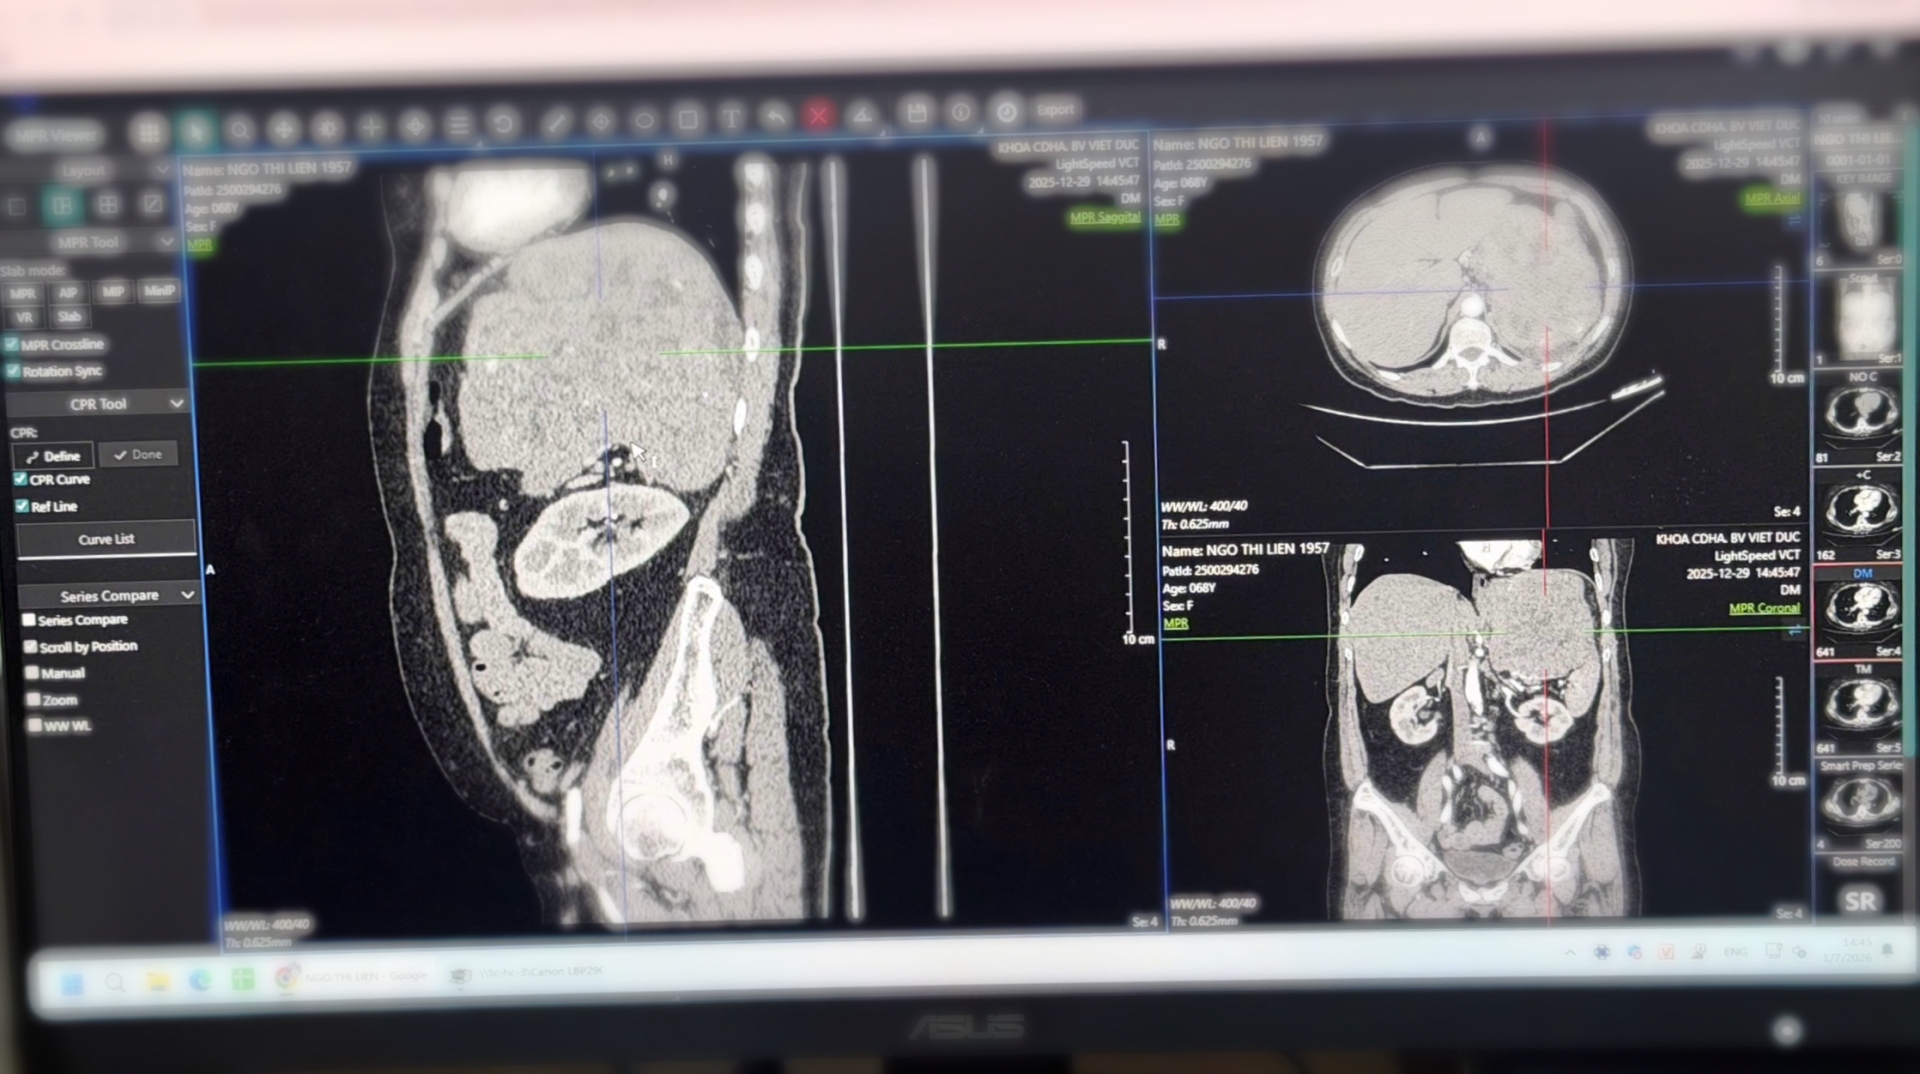

Hình ảnh phim chụp khối u kích thước 20cm của bệnh nhân - Ảnh: BVCC.

Trước đó, người bệnh được phát hiện có khối u sau phúc mạc (một lớp màng mỏng bao phủ toàn bộ các cơ quan bên trong ổ bụng và hố chậu) kích thước khoảng 20cm khi thăm khám tại Bệnh viện Đa khoa Hải Phòng. Nhận thấy tính chất phức tạp của bệnh lý, gia đình đã chuyển bệnh nhân lên Bệnh viện Hữu nghị Việt Đức để điều trị chuyên sâu.

Sau khi thăm khám, hội chẩn và đánh giá kỹ lưỡng bằng các phương tiện chẩn đoán hình ảnh hiện đại, các bác sĩ chỉ định phẫu thuật cắt bỏ toàn bộ khối u. Theo các chuyên gia, đây là một trong những ca mổ khó trong ngoại khoa do khoang sau phúc mạc rộng, khối u thường phát triển âm thầm trong thời gian dài và dễ chèn ép các mạch máu lớn, thận, ruột cũng như hệ thần kinh.